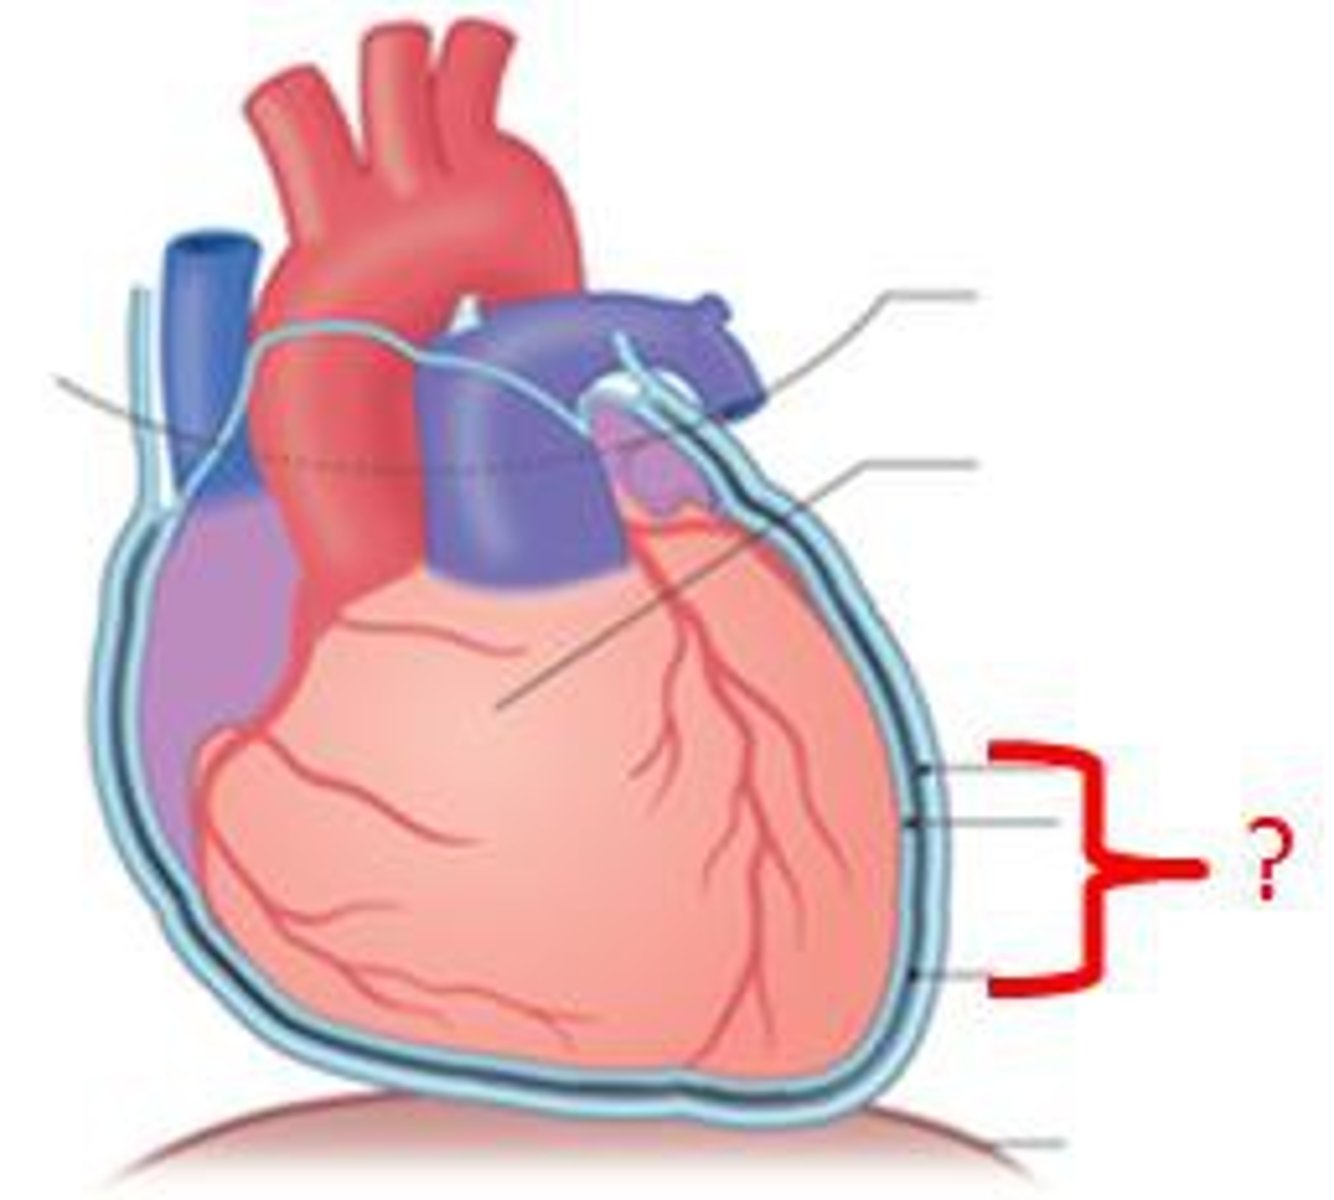

4 Parts of the Heart's Conduction System

- Sinoatrial (SA) node

- Atrioventricular (AV) node

- Bundle of His

- Purkinje fibers

Sinoatrial (SA) Node

Pacemaker of the heart conduction system, located at the right atrium (light blue)

Atrioventricular (AV) Node

The part that relays electrical impulses from atria into the bundle of his in the heart's conduction system; delayed slightly (yellow)

Bundle of His

Part of the heart's conduction system that transmits the cardiac impulse from the atrioventricular node to the purkinje fibers (red)

Purkinje Fibers

Fibers in the ventricles that transmit impulses to the right and left ventricles, causing them to contract